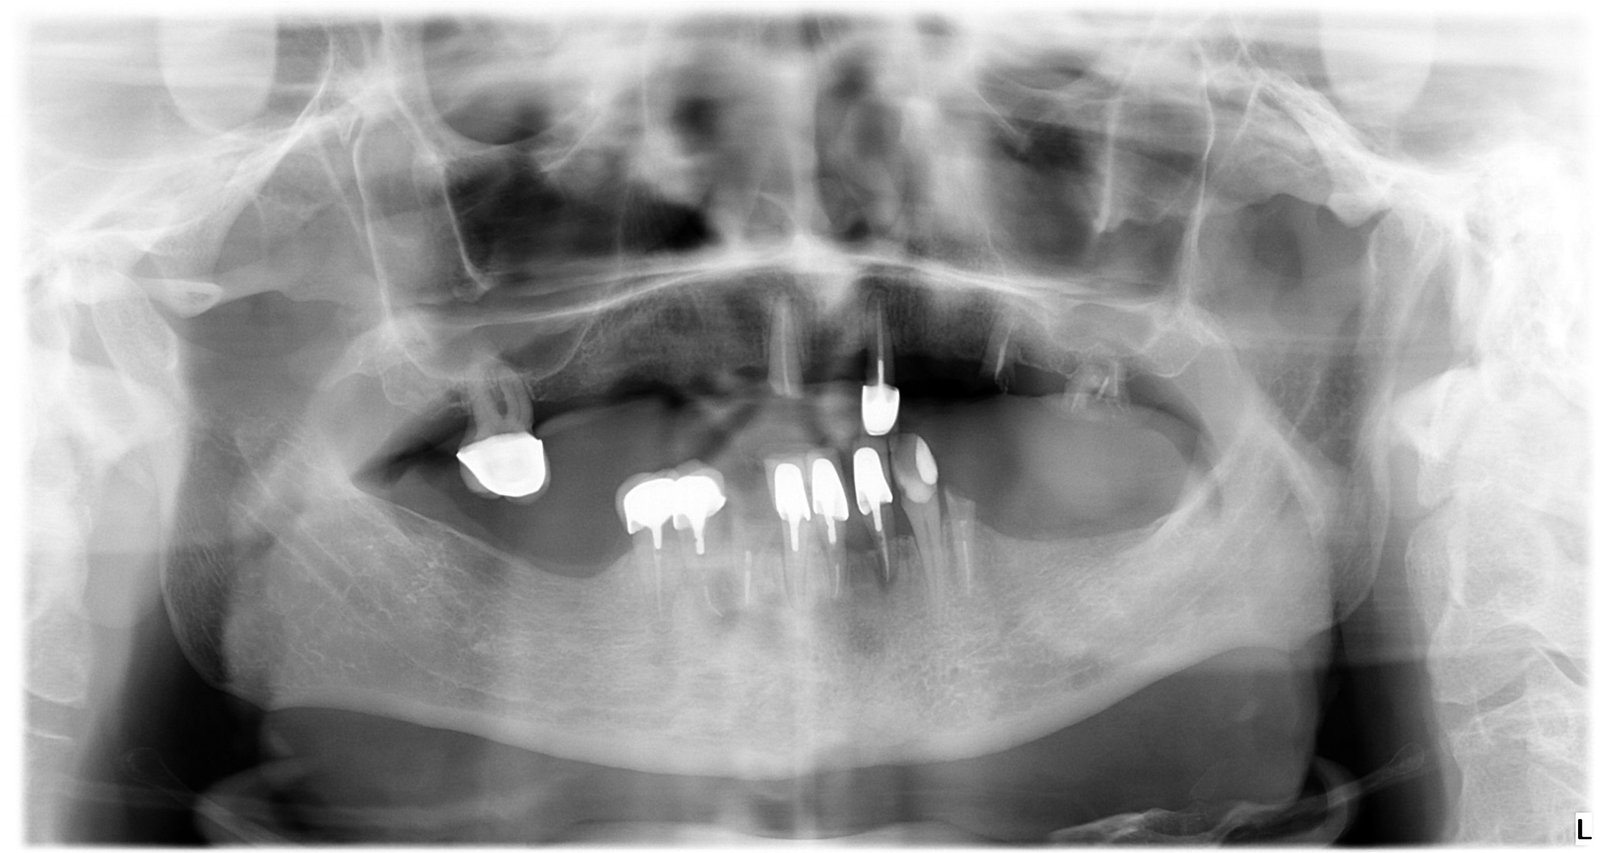

Caso 1 - caso de Implantes dentales

El paciente acudió a consulta con la ausencia de varias piezas dentales que dificultaban la masticación y afectaban a la estética de su sonrisa. Con la colocación de implantes dentales conseguimos recuperar dientes fijos, funcionales y de aspecto natural, devolviéndole seguridad y comodidad al sonreír.

En esta imagen se aprecia la ausencia de piezas dentales y el estado inicial del hueso, lo que permitió planificar un tratamiento implantológico preciso y seguro.